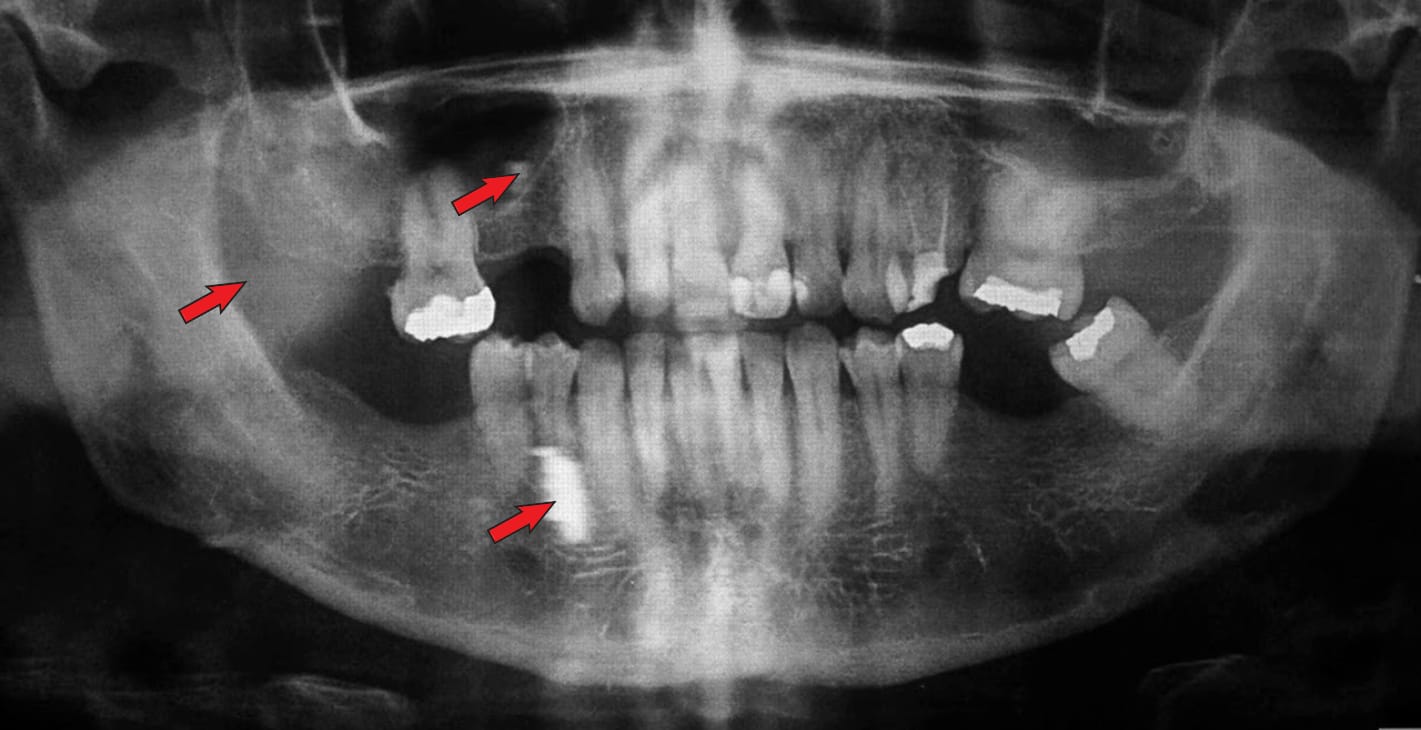

Una imagen fantasma consiste en un artefacto radiopaco que se visualiza en una imagen panorámica y es causado por la doble penetración del haz de rayos X en un objeto. Esta imagen fantasma se parece a la imagen real, pero aparece en el lado opuesto de la película, es más grande y más alta que la imagen real y además es difusa.

Imagen 1: imagenes fantasma